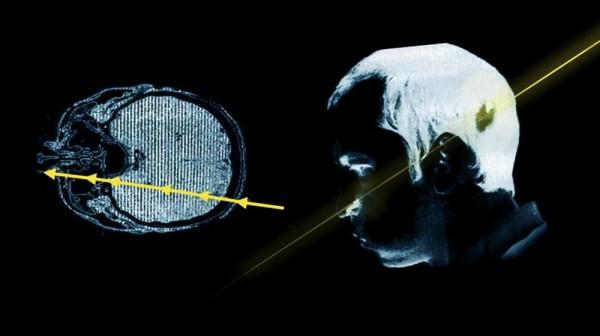

在這位物理學家將頭探進去的一剎那,還在管道內以接近光速執行的高能質子束瞬間從他的左後腦穿到了左臉。

這個高能質子束大約包含十的十二次方數量級的高能質子脈衝,其攜帶的輻射高達20萬拉德,從理論上來說,500拉德的輻射就足夠使一個成年人致死,所以20萬拉德,理論上能讓一個人死400回。

邦格里斯基的好運氣,後來被歸功於質子束的“快準狠”,因為根據後來的研究,轟擊他的質子束直徑只有10的負15次方米,在穿過邦格里斯基大腦的瞬間,質子束還沒來得及釋放輻射就又穿過去了,所謂的20萬拉德輻射只是看起來嚇人,真正作用到邦格里斯基身上的只是一小部分而已。